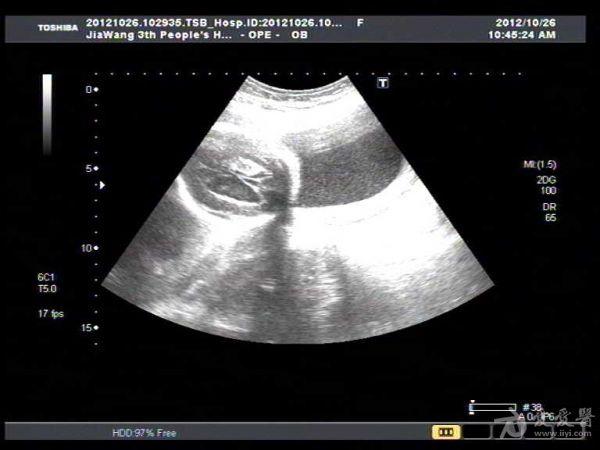

此孕妇22岁,于孕六月来我院产检,可见胎儿侧脑室扩张积液约1.4Cm,遂告知小孩脑

积水,此孕妇接着去我们当地三甲医院检查,也被告知胎儿脑积水,建议引产。